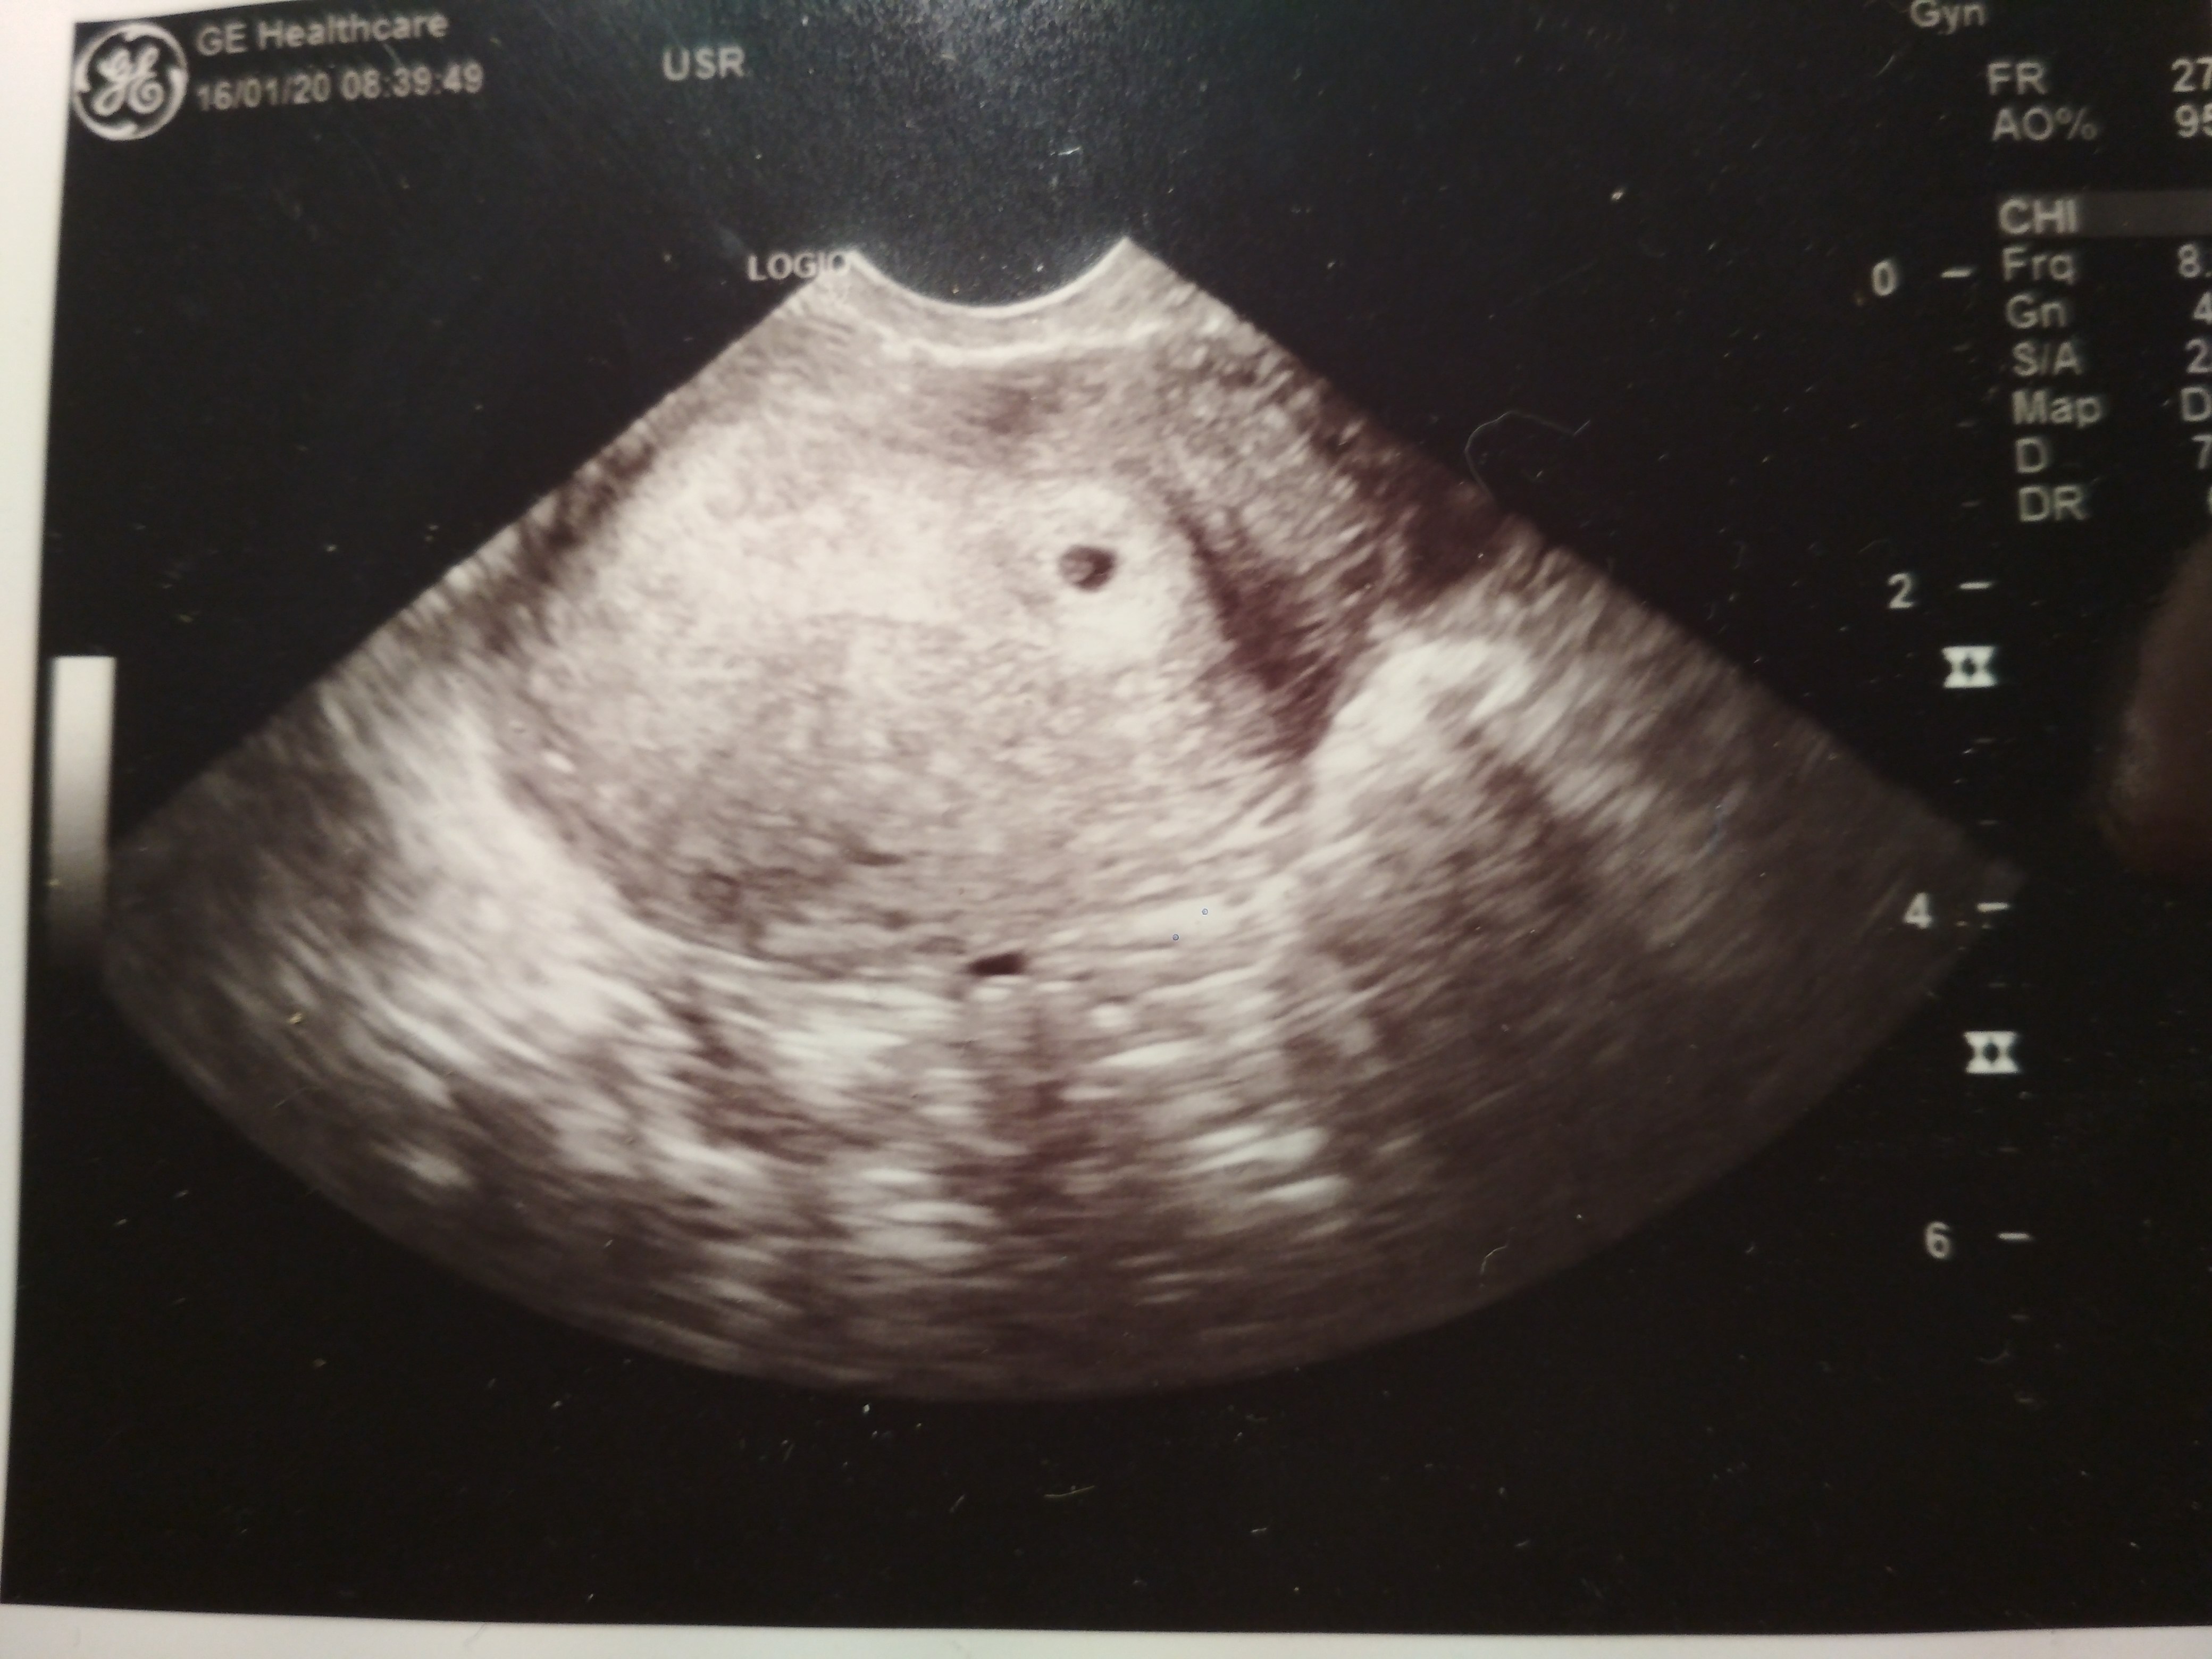

A mnie wcozrajsza wizyta nie dawala spokoju i poszlam dzis po pracy prywatnie do takiej starszej babeczki, czasem wpadalam do niej po recepte czy cos i o niebo lepsze podejscie

Z usg 5,17 mm i 6tydz, termin na 10 wrzesnia, tak jak powinno byc z moich wyliczen

Wczoraj u tamtego 2 mm i 5+3 , termin 18 wrzesnia....

Takze jestem juz spokojna i ciesze sie moja polcentymetrowa dzidzia !